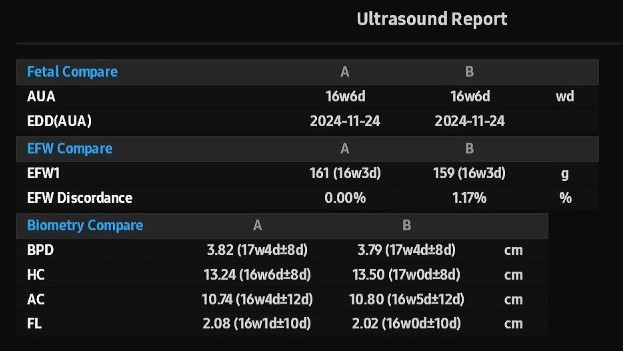

쑥쑥이는 161g, 쭉쭉이는 159g으로 둘의 차이는 1.17%로 주수에 맞게 아주 잘 크고 있었어요.